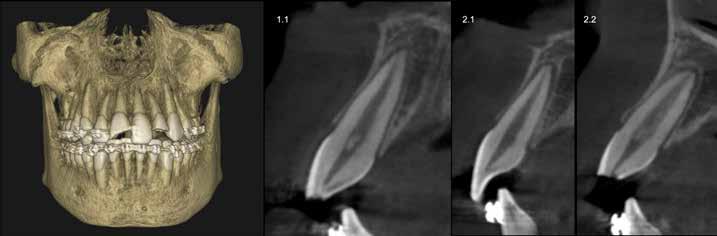

En la exploración clínica se observó ortodoncia fija con varios brackets descementados y el arco desajustado. Los hallazgos incluyeron:

Fractura coronal complicada (afectación de esmalte, dentina y pulpa) en los dientes 1.1 y 2.2, con sensibilidad aumentada.

Luxación lateral del 2.1 (el paciente refirió haberse reposicionado el diente por iniciativa propia).

Se realizó una tomografía computarizada de haz cónico (TCHC; Carestream 9600, Carestream Dental), donde se observaron fracturas coronales complicadas en 1.1 y 2.2, luxación lateral de 2.1 sin fractura de la cortical vestibular (Figura 3). No se detectaron otras

alteraciones óseas o dentarias. En las pruebas de sensibilidad al frío, los dientes 1.3, 1.2, 2.1 y 2.3 respondieron de forma normal, mientras que 1.1 y 2.2 mostraron respuesta exacerbada debido a la exposición pulpar.

Diagnóstico definitivo:

1.1: fractura coronal complicada (exposición pulpar de 3–4 mm).

2.1: luxación lateral sin afectación de la cortical vestibular.

2.2: fractura coronal complicada (exposición pulpar de 1 mm).

Figura 3: Capturas sagitales del CBCT de los dientes 1.1, 2.1 y 2.2.